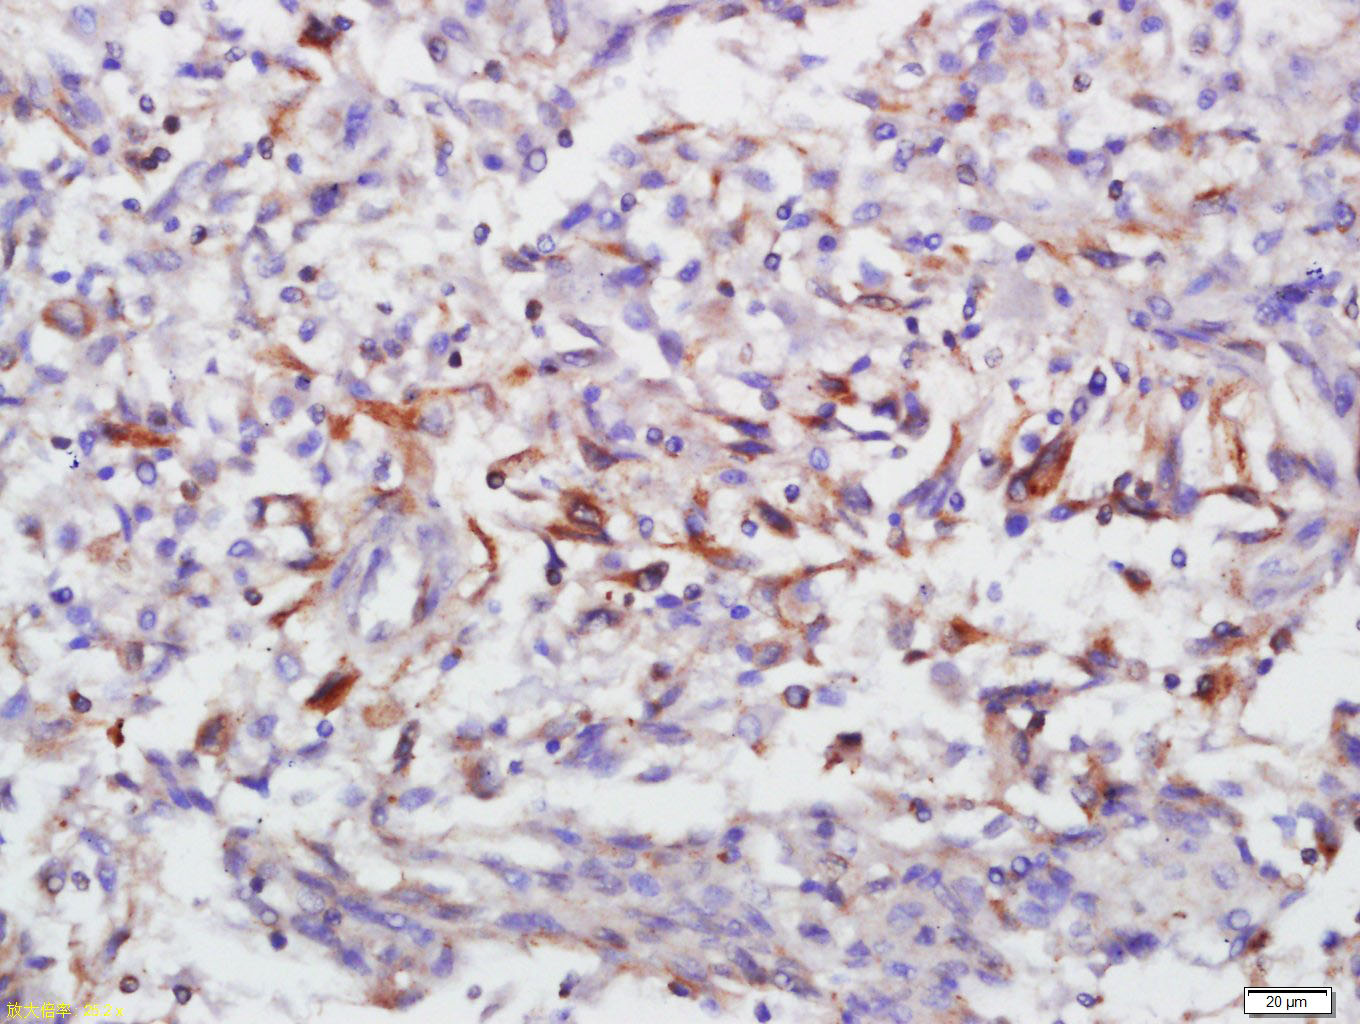

Tissue/cell: rat lung tissue; 4% Paraformaldehyde-fixed and paraffin-embedded; Antigen retrieval: citrate buffer ( 0.01M, pH 6.0 ), Boiling bathing for 15min; Block endogenous peroxidase by 3% Hydrogen peroxide for 30min; Blocking buffer (normal goat serum,C-0005) at 37← for 20 min; Incubation: Anti-Annexin V Polyclonal Antibody, Unconjugated(bs-0450R) 1:500, overnight at 4⒉C, followed by conjugation to the secondary antibody(SP-0023) and DAB(C-0010) staining

Tissue/cell: human Neurological glioblastoma; 4% Paraformaldehyde-fixed and paraffin-embedded; Antigen retrieval: citrate buffer ( 0.01M, pH 6.0 ), Boiling bathing for 15min; Block endogenous peroxidase by 3% Hydrogen peroxide for 30min; Blocking buffer (normal goat serum,C-0005) at 37← for 20 min; Incubation: Anti-Annexin V Polyclonal Antibody, Unconjugated(bs-0450R) 1:500, overnight at 4⒉C, followed by conjugation to the secondary antibody(SP-0023) and DAB(C-0010) staining